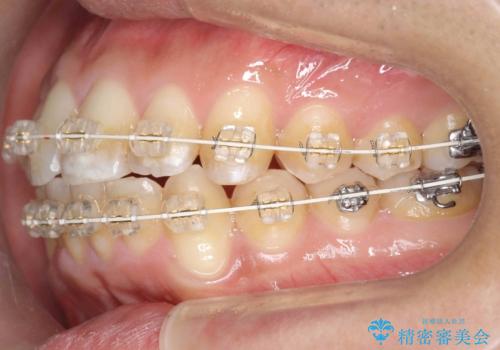

歯を抜かない矯正 奥歯のすれ違い咬合 下の八重歯

- 矯正装置

- 審美装置

- 前歯のガタガタを主訴に来院。

奥歯はすれ違ってしまっていました。

口元も出ておらず、非抜歯を希望されたため、IPR(歯を削る処置)でスペースを確保しました。

上顎両側7番(一番奥の歯)はすれ違っており、虫歯になっていました。